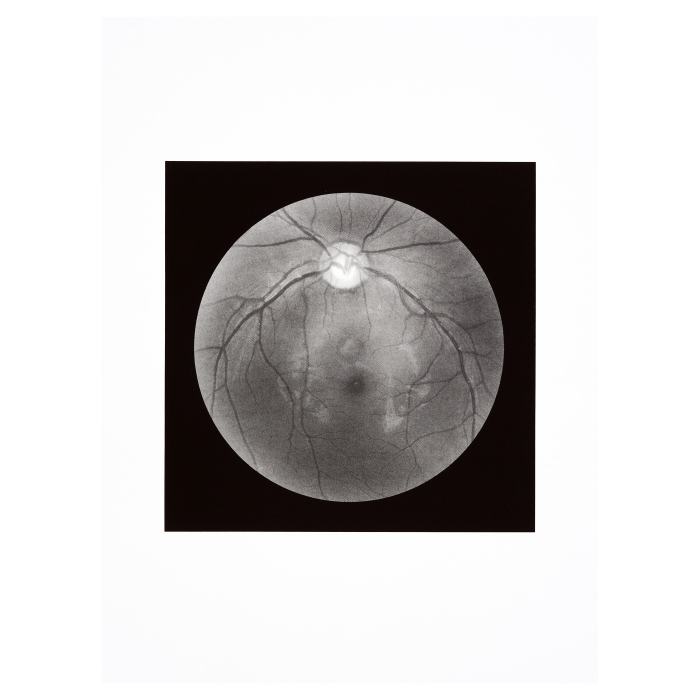

Tache aveugle I, 2012

Manon Bellet

Tache aveugle II, 2012

Liesje De Laet